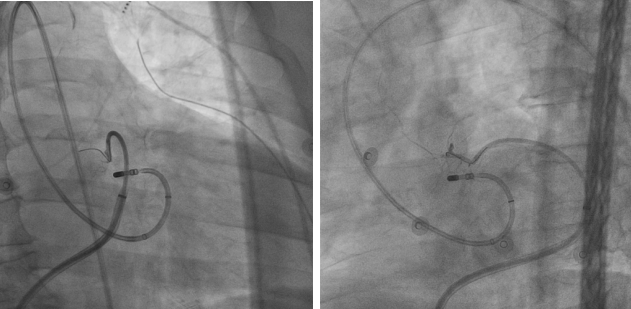

该技术操作极其精细复杂,术者需先将一根细如发丝的导管,经动脉逆行送入心脏的冠状静脉;通过冠状静脉造影,找到为室早病灶供血的微小血管;随后,将少量无水酒精精准注入该血管,造成病灶区域的化学性坏死,从而达到根治心律失常的目的。